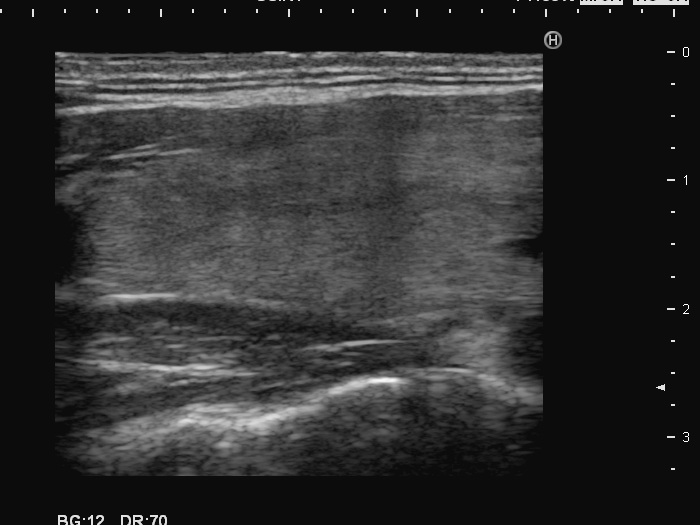

Left lobe, longitudinal scan

This is the usual course of Graves' disease regarding the change in echo pattern - before, during and after the activity of the autoimmune process. The only exception is the change in the size of the thyroid. In most cases, the thyroid increases during the activity of the disease, then returns to normal. However, in this patient the age counts: at the first examination, the patient was only 15-year-old.